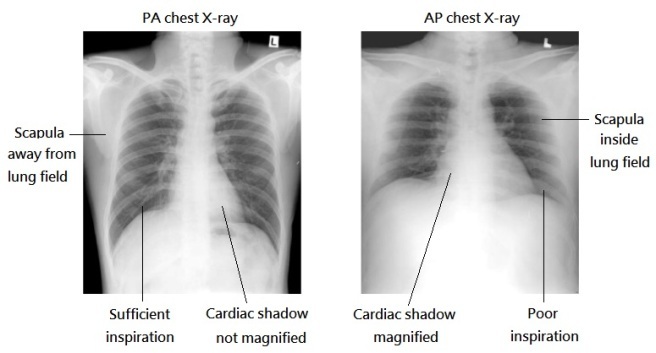

how do you tell if an x-ray is PA or AP?

who is more likely to have an PA or AP x-ray?